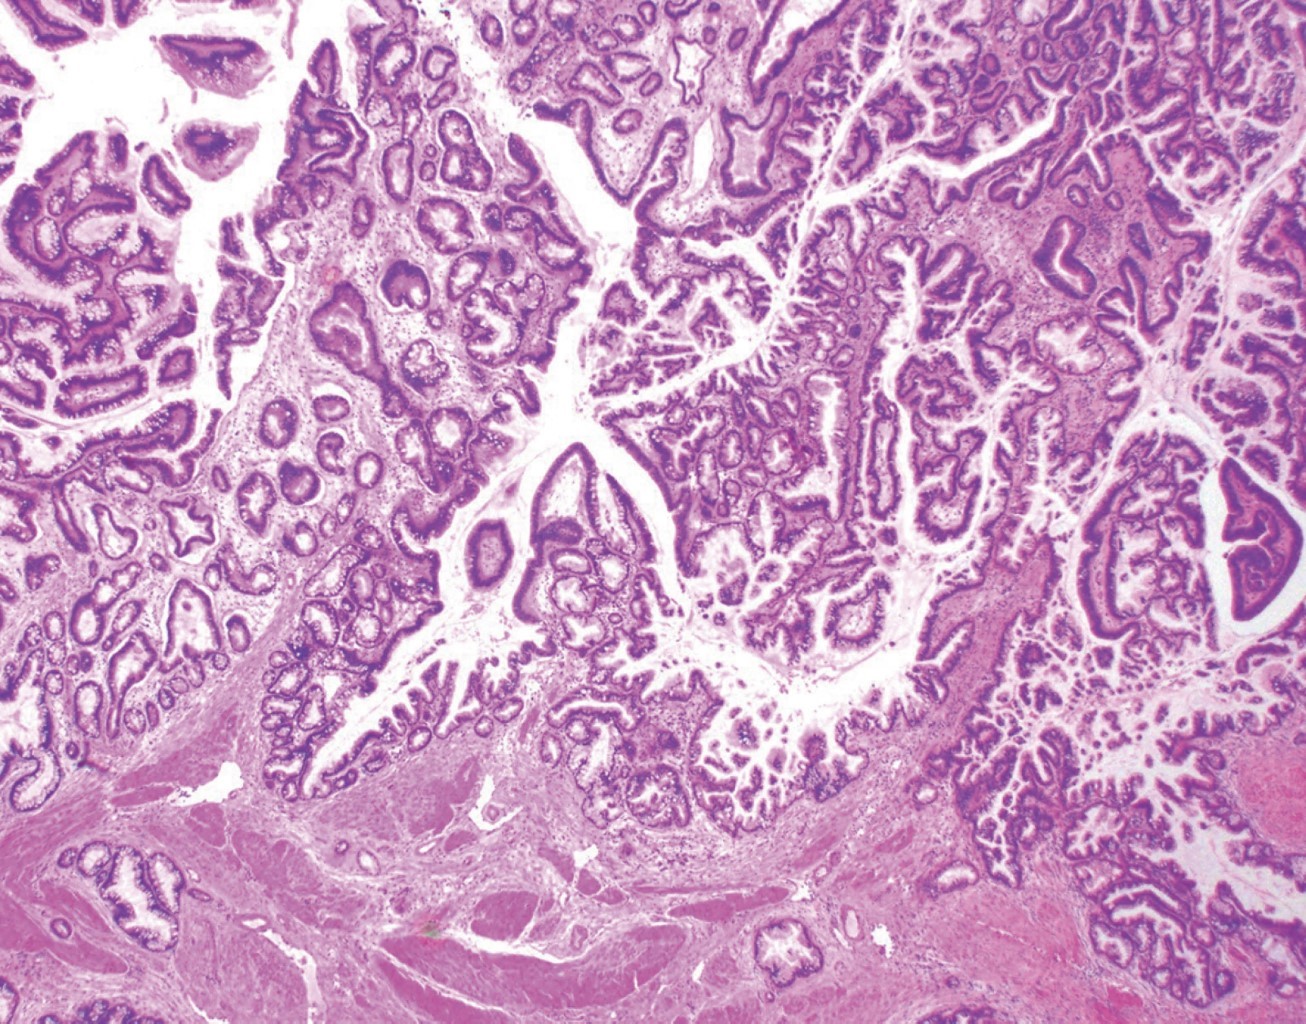

Masculino de 64 años, quien inicia su padecimiento con ictericia, negando otra sintomatología, llama la atención que se manifesta durante al menos tres días previos a su llegada a urgencias, su exploración física sin alteraciones, los laboratorios revelan una bilirrubina total de 25 mg/dl, bilirrubina directa de 22 mg/dl, fosfatasa alcalina 235 UI/l, gamma-glutamil transferasa 157 UI/l, creatinina 2.5 mg/dl, el resto de los laboratorios normales, se le realiza un ultrasonido de abdomen que reporta vesícula biliar mal definida, y dilatación de la vía biliar de 19 mm (Figura 1), se observa lito en colédoco de alrededor de 12 mm. Se integra el diagnóstico de coledocolitiasis, no obstante, se solicitan marcadores tumorales, con reporte de CA 19-9 de +8,000 UI; se solicita colangiorresonancia, la cual evidencia dilatación de vía biliar (vb) de 20 mm, lito de 16 mm a nivel del ámpula, no se reporta morfología de la vesícula biliar (VB), paciente candidato a colangiopancreatografía retrógrada endoscópica (CPRE) según el servicio de Gastroenterología. Se le realiza CPRE sin poder extraer lito, se programa para colecistectomía con exploración de vía biliar, el transoperatorio revela biliperitoneo, lisis de VB, fístula colecistocoledociana (Figura 2), litio único de 15 mm, se coloca sonda T, no se cuenta con servicio de cirugía hepatopancreatobiliar, por lo que no se realiza reparación definitiva, colangiografía transoperatoria revela paso de material de contraste a duodeno, sin fugas aparentes por orificio fistuloso (Figura 3), evolución posoperatoria favorable, el drenaje por sonda T en promedio 500 ml por día con disminución progresiva, con mejoría de hiperazoemia, con flujo urinario mayor a 0.5 ml/kg/h, colangiografía posoperatoria sin fugas, paso de medio de contraste a duodeno, reporte de patología revela adenocarcinoma de vesícula moderadamente diferenciado con infiltración a muscular (Figura 4). El paciente rechaza tratamiento médico y decide egreso voluntario, comprende y acepta los riesgos, no contamos con seguimiento a largo plazo.

El diagnóstico preoperatorio es difícil en general, éste suele sospecharse en pacientes mayores con dolor en hipocondrio derecho y síntomas atípicos. El ultrasonido es poco sensible para detectar hallazgos, pues posee una precisión tan baja como 11% en algunas series reportadas. Algunos autores mencionan datos sugestivos para SM: VB atrófica, dilatación del CH con VBC de calibre normal (92%). Otros datos indirectos son: dilatación de la VBC mayor a 7 milímetros, con o sin lito mayor a 10 mm en VBC, neumobilia, lito enclavado en Hartmann.7

En caso de CAVB, las calcificaciones invasión luminal, pérdida de la interfase hígado-vesícula, infiltración hepática directa, pared irregular, pólipo vesicular mayor a 10 mm, son los hallazgos conocidos.3 El ultrasonido carece de utilidad para valorar el estadio, es decir, la extensión de la enfermedad.

Figura 1